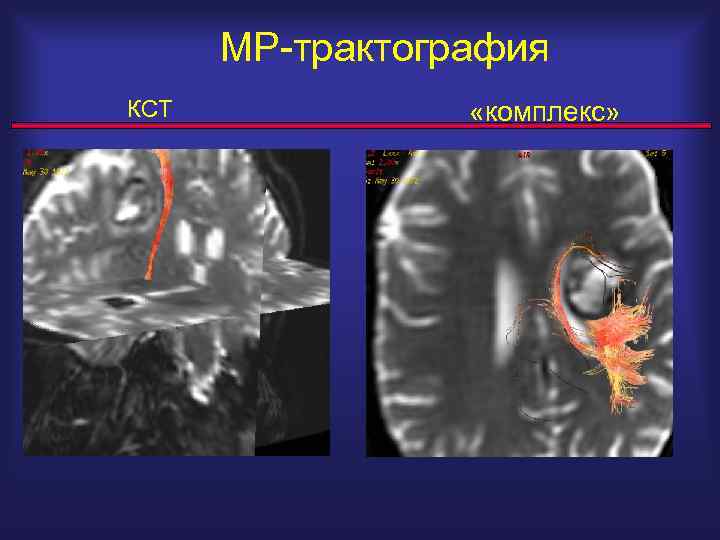

МР-трактография КСТ «комплекс»